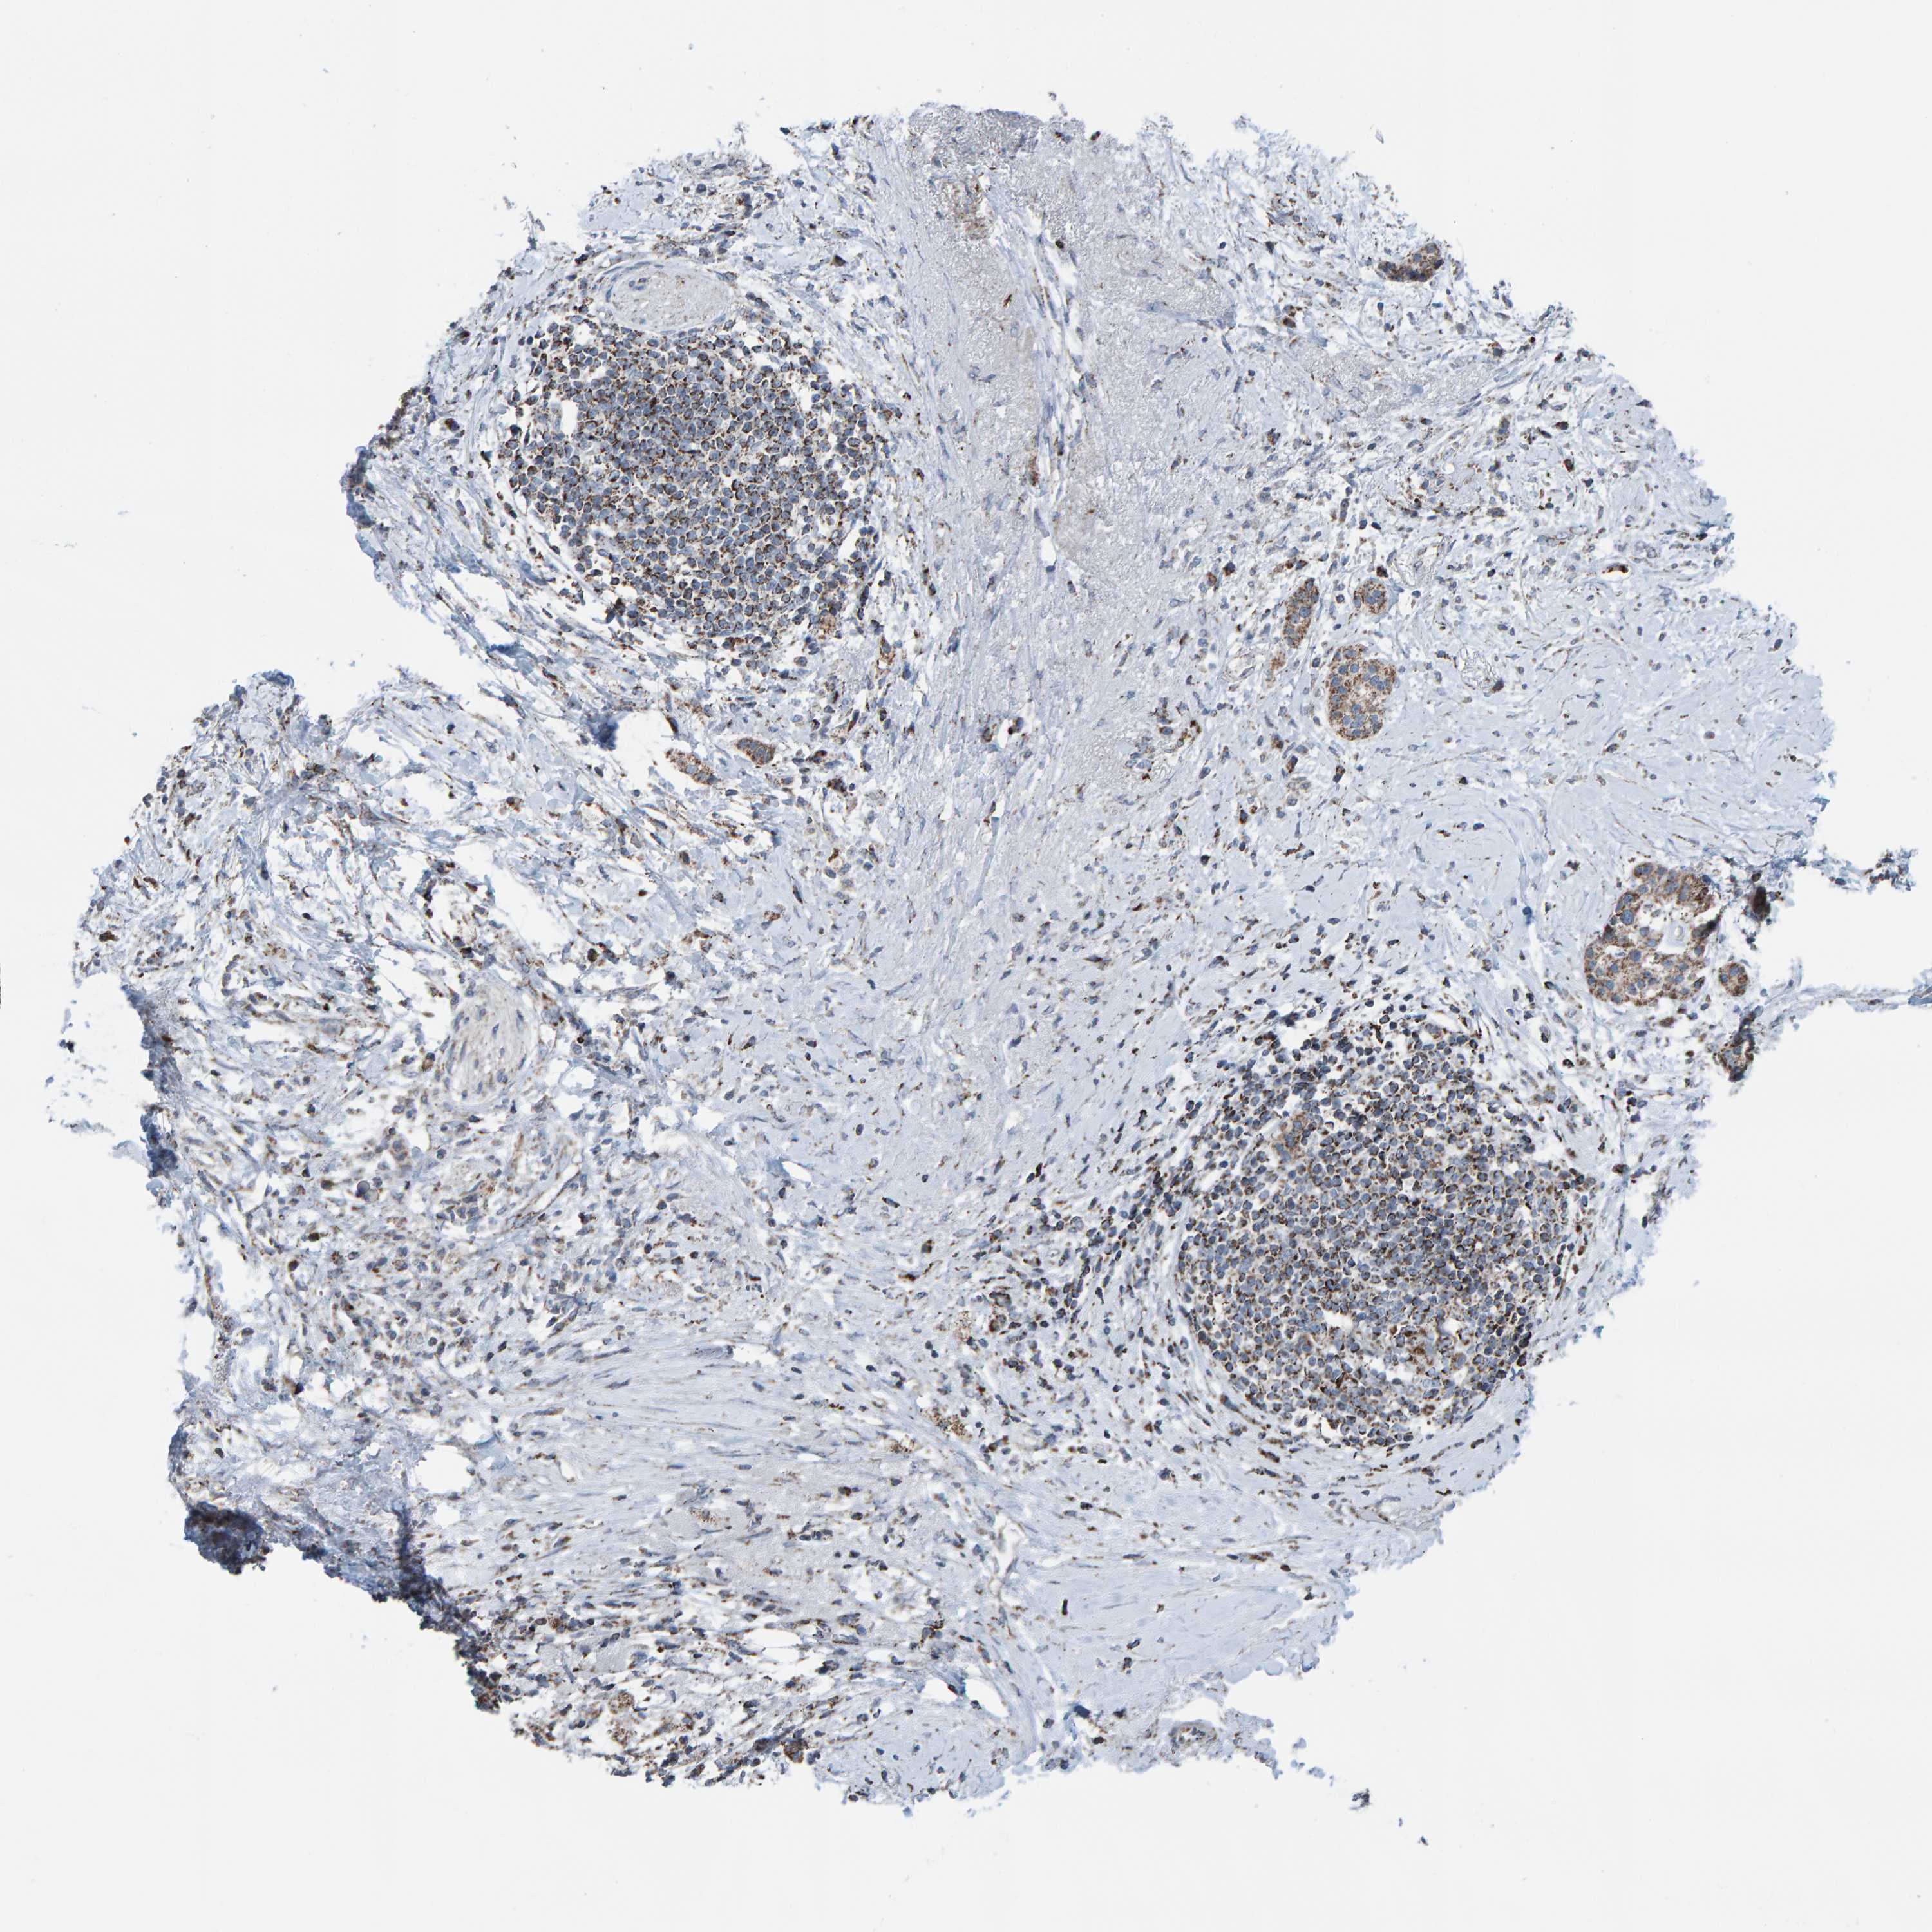

PANCREATIC CANCER - Protein expressioni

A mouse-over function shows sample information and annotation data. Click on an image to view it in a full screen mode. Samples can be filtered based on level of antibody staining by selecting one or several of the following categories: high, medium, low and not detected. The assay and annotation is described here.

Note that samples used for immunohistochemistry by the Human Protein Atlas do not correspond to samples in the TCGA dataset.

Antibody stainingi

Antibody staining in the annotated cell types in the current human tissue is reported as not detected, low, medium, or high, based on conventional immunohistochemistry profiling in selected tissues. This score is based on the combination of the staining intensity and fraction of stained cells.

Each image is clickable and will lead to virtual microscopy that enables deeper exploration of all samples and also displays staining intensity scores, fraction scores and subcellular localization as well as patient and tissue information for each sample.

Antibody HPA023806

Staining

High

Medium

Low

Not detected

Intensity

Strong

Moderate

Weak

Negative

Quantity

>75%

75%-25%

<25%

None

Location

Nuclear

Cytoplasmic/membranous

Cytoplasmic/membranous,nuclear

Adenocarcinoma, NOS